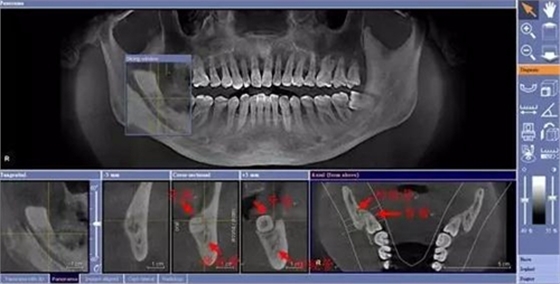

由于智齒的生長位置特殊,導(dǎo)致了拔除難易不同,如智齒出現(xiàn)橫著長或者靠近牙神經(jīng)的話,則難度會較高,一般人只需拍個口腔全景片,但相對于智齒靠近神經(jīng)管的情況,還可能需要拍CT,這都很考驗(yàn)牙醫(yī)的技術(shù)。

下面這兩張圖,據(jù)說拔牙費(fèi)時1.5小時,收費(fèi)14000元。